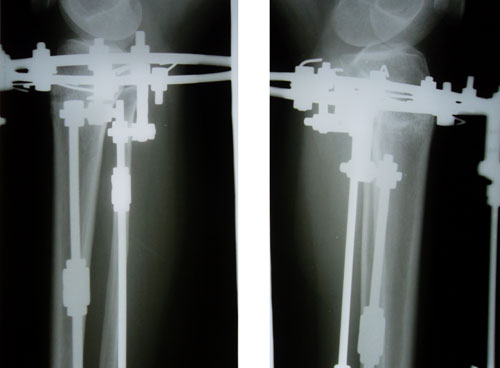

Дата операции 16.06.2014г.

Дата снятия аппаратов 04.11.2014г.

Срок лечения 138 дней.

рентген в день снятия аппаратов.